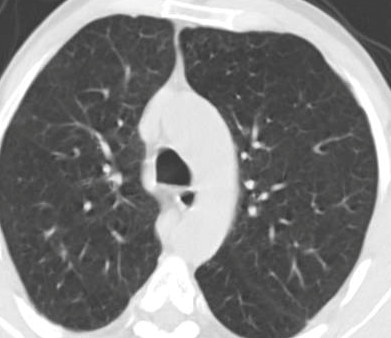

In a similar way, we consider classifying the test CT scans from the COVID-19 dataset by the DenseNet169 model and highlight the important regions considered for predictions. We present the original CT images and their localization maps in Figure 13. We can also see that our model is capable to detect the COVID-19 related regions as marked (small square in some images) by expert radiologists.

Figure 16 shows various CT scans where only one lung is visible. The CT scans are also extracted from the paper [58] and show different CT manifestations of COVID-19 pneumonia marked by red squares. The InceptionV3 model is capable to classify them correctly as COVID-19, although it is trained on CT scans where the entire lung is visible. Intriguingly, when applying Grad-CAM we can see that all regions of abnormalities are accurately localized. This also proves the potential of our model to detect COVID-19 abnormalities in CT images outside the dataset used for training.